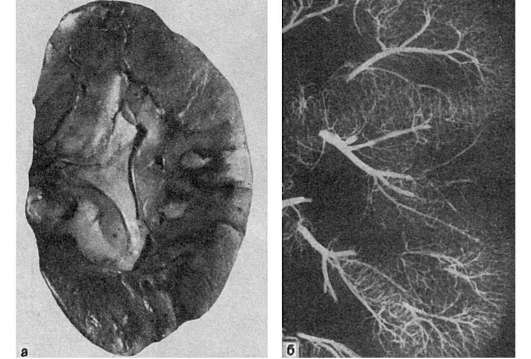

Инфаркт селезенки:

а - ишемический инфаркт в виде светлого треугольного участка, обращенного основани- ем к капсуле; б - ангиорентгенограмма той же селезенки. Отсутствие сосудов в области инфаркта